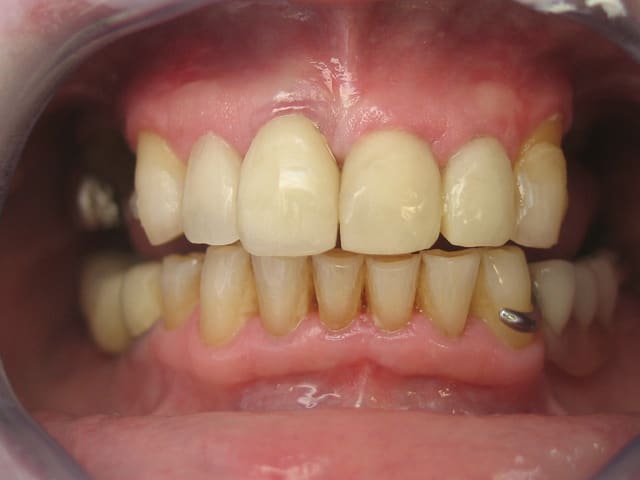

je précise que la réhabilitation du secteur ant est faite dans le cadre d'une reconstruction globale, ci joint la derniere radio et projet proth.

Capture ley5kt - Eugenol

Goarrin j 20120515 785 nfxhtp - Eugenol